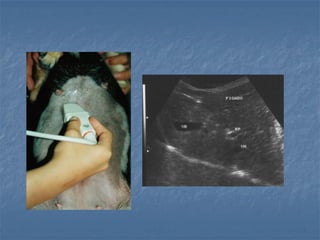

Vesícula biliar: técnica de varredura

 transdutor de alta resolução

 Planos de varredura: longitudinal e

transversal em janelas sub-xifoide e

intercostal no 7 EIC